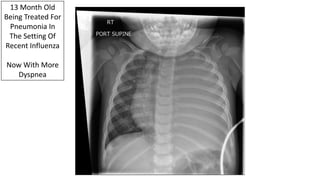

13 Month Old

Being Treated For

Pneumonia In

The Setting Of

Recent Influenza

Now With More

Dyspnea

Parapneumonic Effusion With Shift

500 cc Of

Purulent

Chest Tube

Output